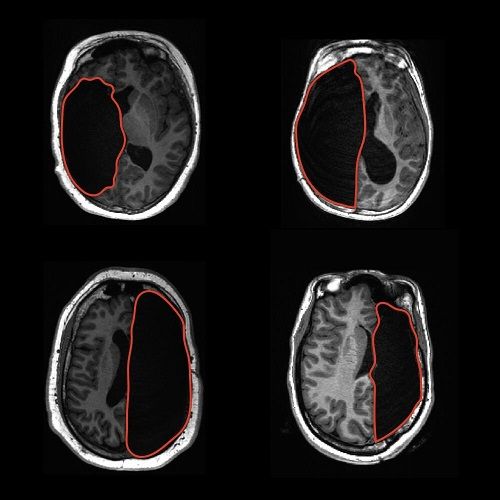

上一行图:切除左半球。下一行图:切除右半球。图片来源:物理学家组织网

当大脑在高度可塑性的情况下被迫改变和适应时,会发生什么呢?为了回答这个问题,研究人员观察了一组特殊的患者,他们在童年时期接受了手术切除一侧大脑半球以控制癫痫发作。

研究人员分别测试了参与者识别两个单词和两张人脸的能力。结果发现,剩下的大脑半球支持这两种功能。大脑半球切除者和对照受试者的单词和人脸识别能力不 同,但差异不到10%,平均准确率超过80%。无论切除哪个大脑半球,参与者在面部和单词识别上的准确率都是相当的。